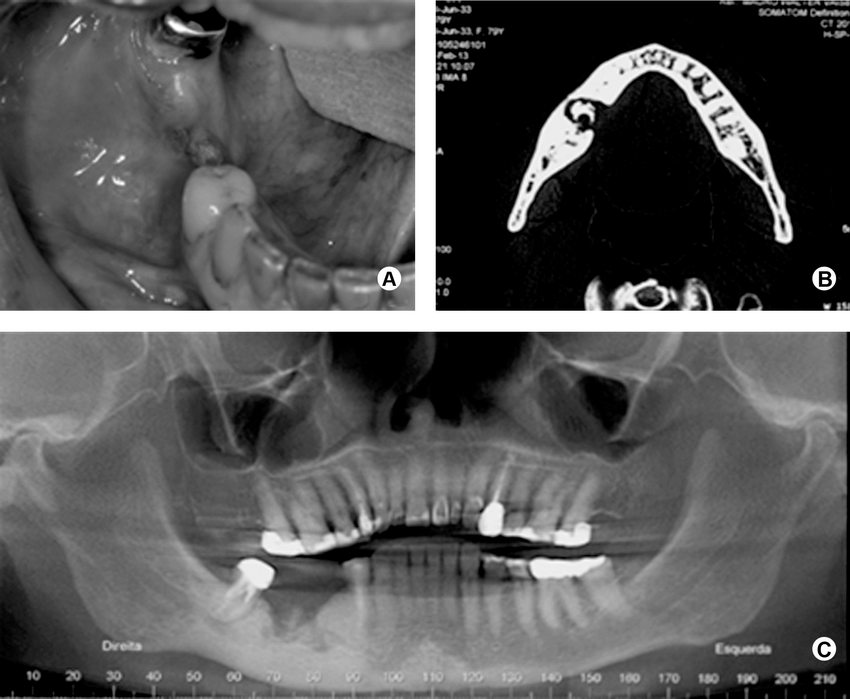

A 63-year-old woman presented with exposed bone sequestrating from the mandibular alveolar ridge. Serum biochemistry showed that her alkaline phosphatase level was elevated 20-fold over the top of the normal range.

Also, if someone has a long-term bone infection in their jaws, this can cause a problem called bone sequestration. It means that a piece of dead bone gets separated from the healthy bone.